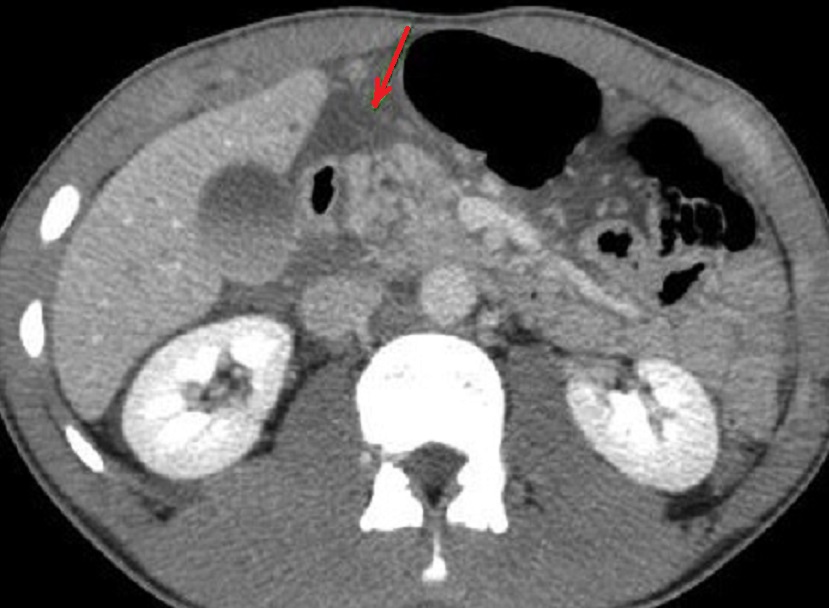

Traumatisme de la tete du pancreas avec

hematome hyperdensite legere intra-pancreatique ( fleche )

. La tete et le corps du pancreas est volumineuse a

hypodensite et non homogene Image radiologique TDM en coupe axiale |